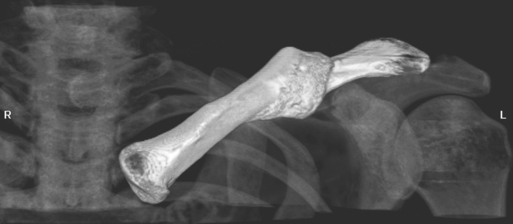

The humerus is a long bone that articulates with the scapula superiorly and the radius and ulna inferiorly. It consists of a body or shaft, a lower end (distal end), and an upper (proximal) end (Figure 9.13). The proximal end is formed by the head of the humerus. Two tubercles project from the humeral head to provide attachment sites for tendons and ligaments. The lesser tubercle is located on the anterior surface of the humeral head, whereas the greater tubercle is located on the lateral surface of the humeral head (Figures 9.12 through 9.15). The tubercles are separated by the intertubercular (bicipital) groove, which is bounded by the crests of the lesser and greater tubercles as it descends the humerus (Figures 9.9 and 9.13 through 9.15). The humerus has two necks, the more proximal anatomic neck and the surgical neck, located inferior to the tubercles just distal to the humeral head (Figures 9.13 and 9.16). In the middle of the body or shaft of the humerus, on the anterior surface, is the roughened area of the deltoid tuberosity that gives attachment for the deltoid muscle (Figure 9.13).